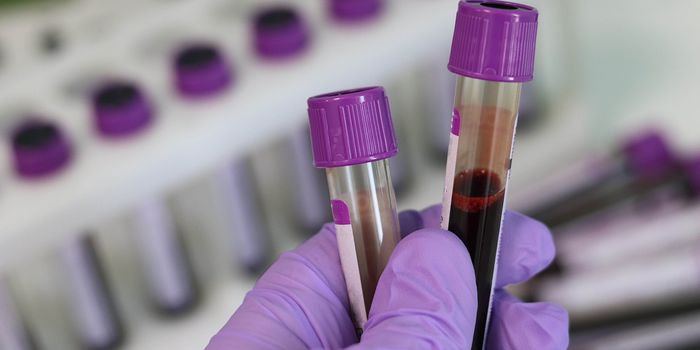

MAR 11, 2024NeuroscienceA blood test detected when individuals had been awake for 24 hours or more with 99.2% accuracy. The corresponding study ...